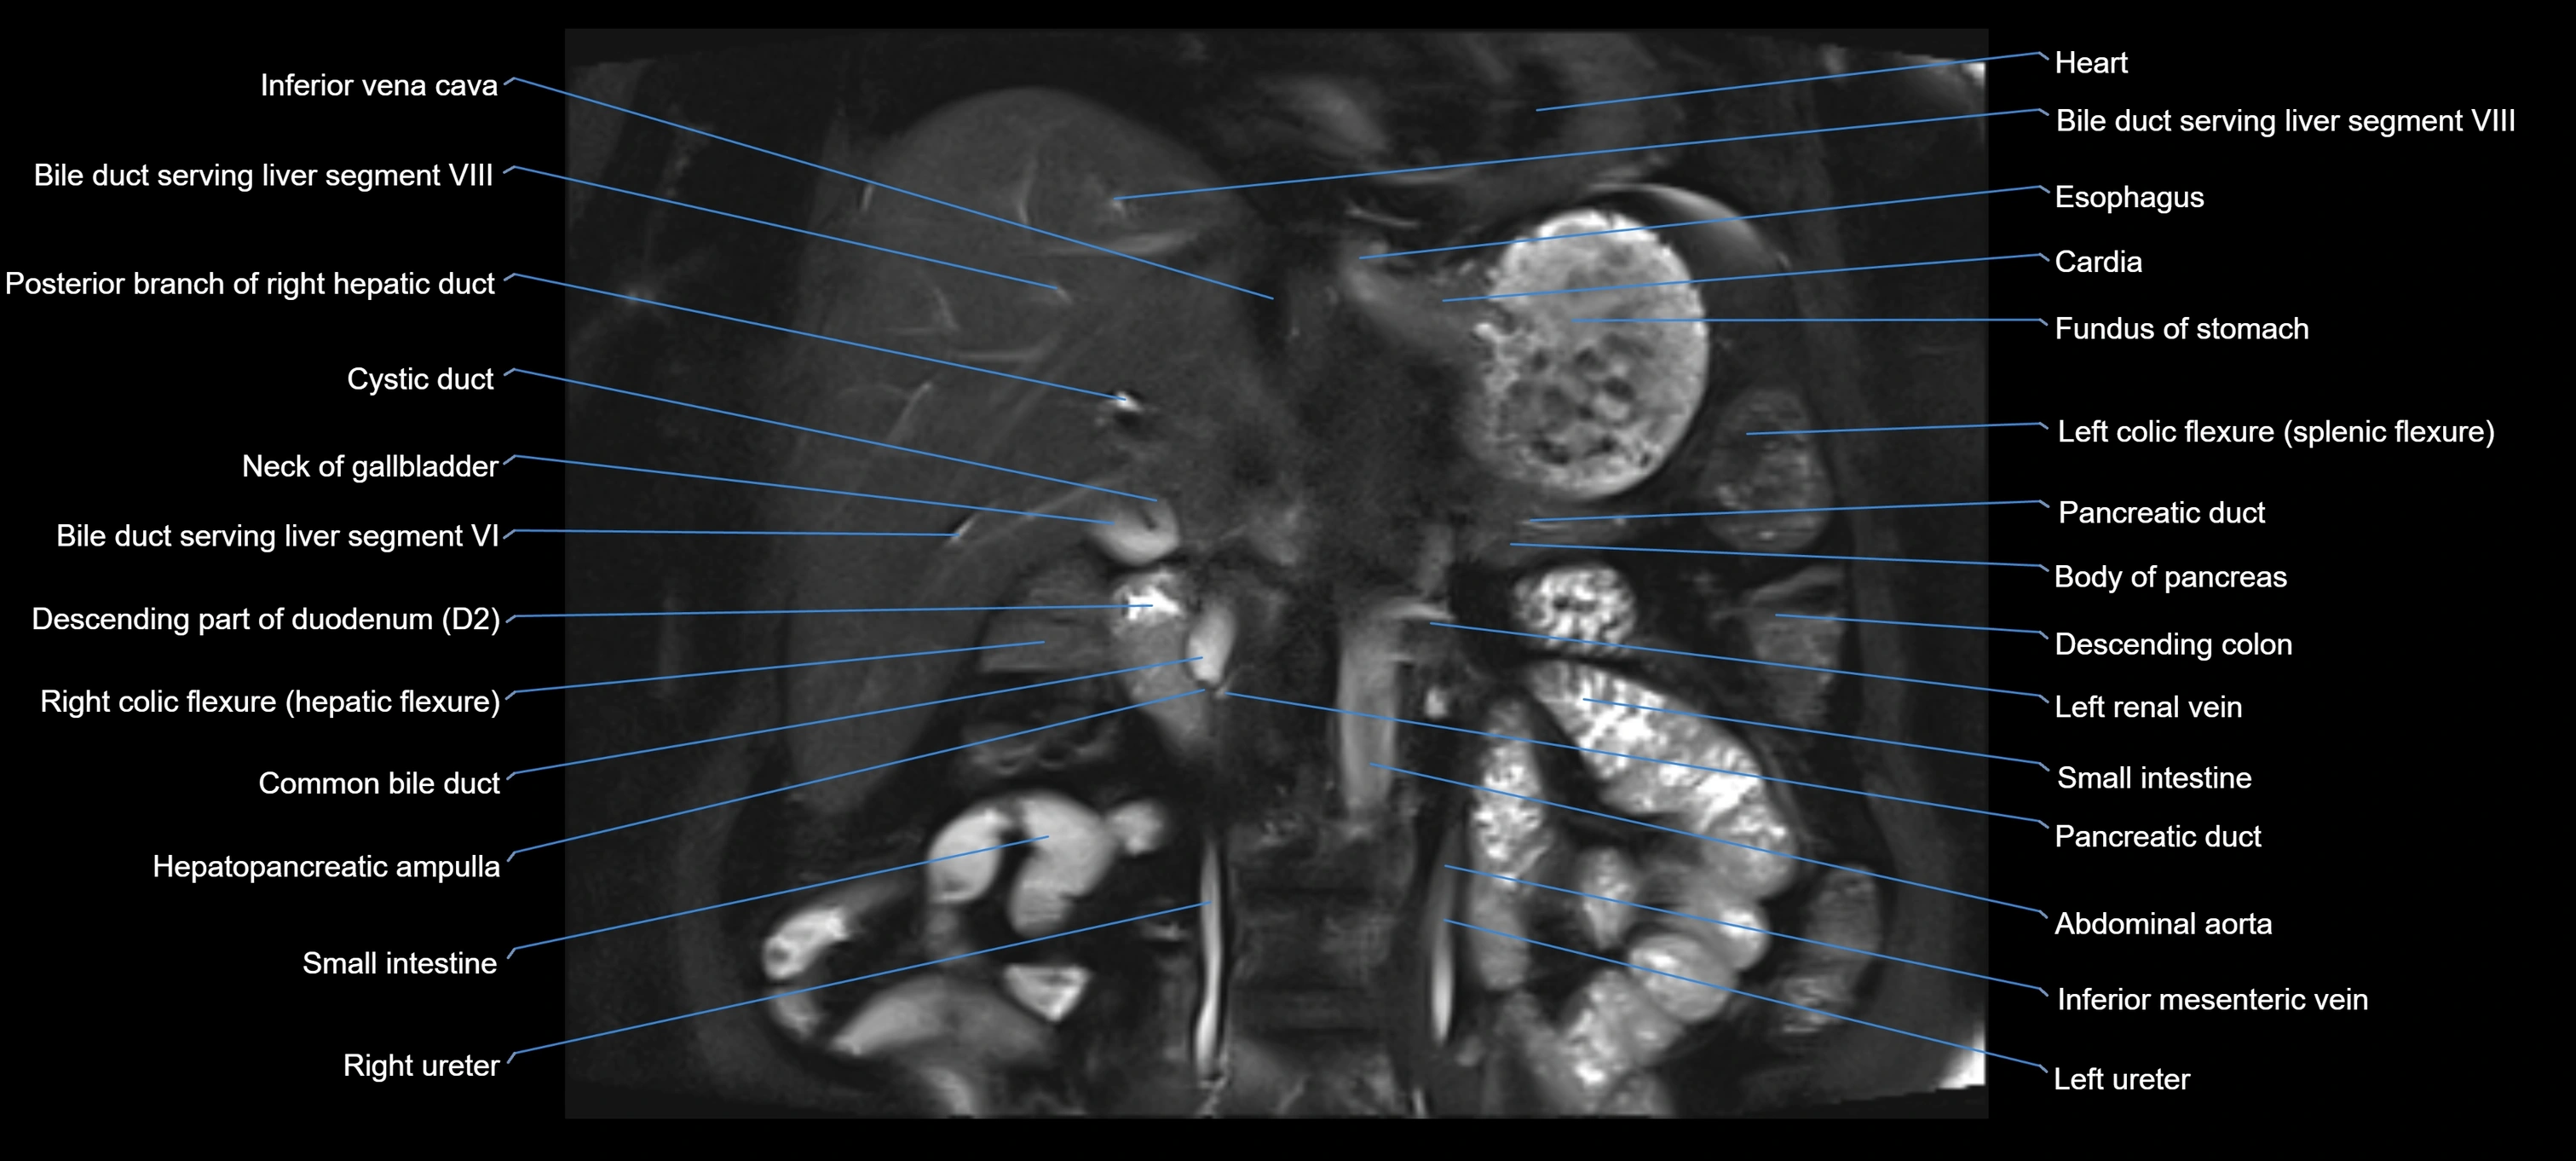

MRI image

image